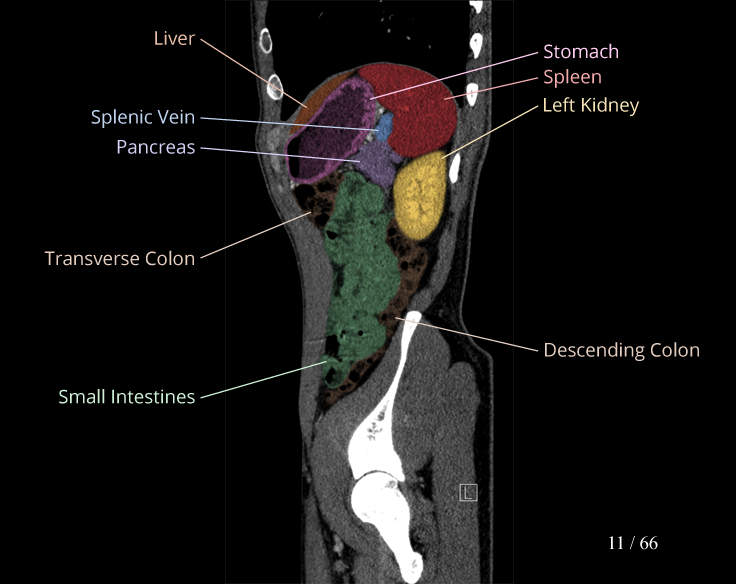

Body

Covers abdominal CT anatomy.